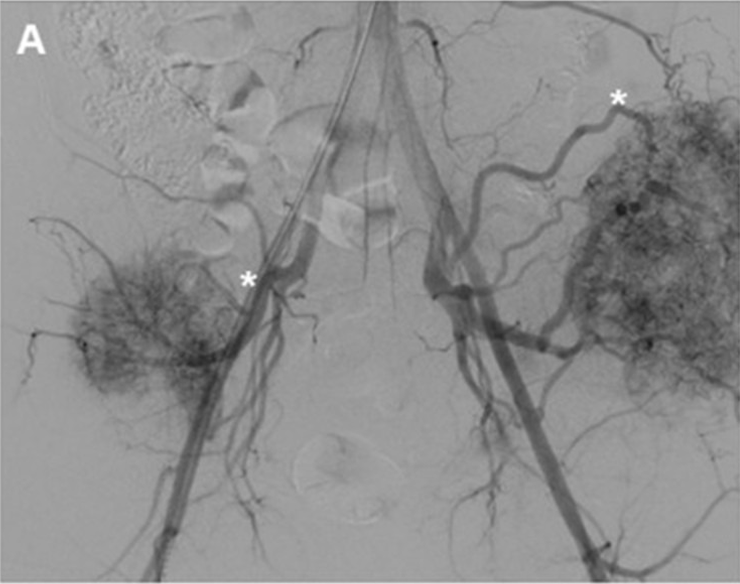

Since the 1970s, arterial embolization has progressively gained a central role in the management of metastatic bone disease, representing a safe alternative for patients who are not candidates for surgery. By selectively occluding tumor-feeding arteries, embolization induces devascularization and tumor shrinkage, combining palliative benefits with a degree of local tumor control (Figure 1).

Figure 1: A 56-year-old male patient with two large metastases from renal cancer localized in both iliac bones. (A) panoramic DSA angiogram showing two large hypervascular masses supplied by hypertrophic vessels arising mainly from in internal iliac artery (asterisk). (B) Pre-embolization CT-scan demonstrating the two large lytic lesions of both iliac bones and (C) 6-month follow-up CT showing marked calcification of the lesions.